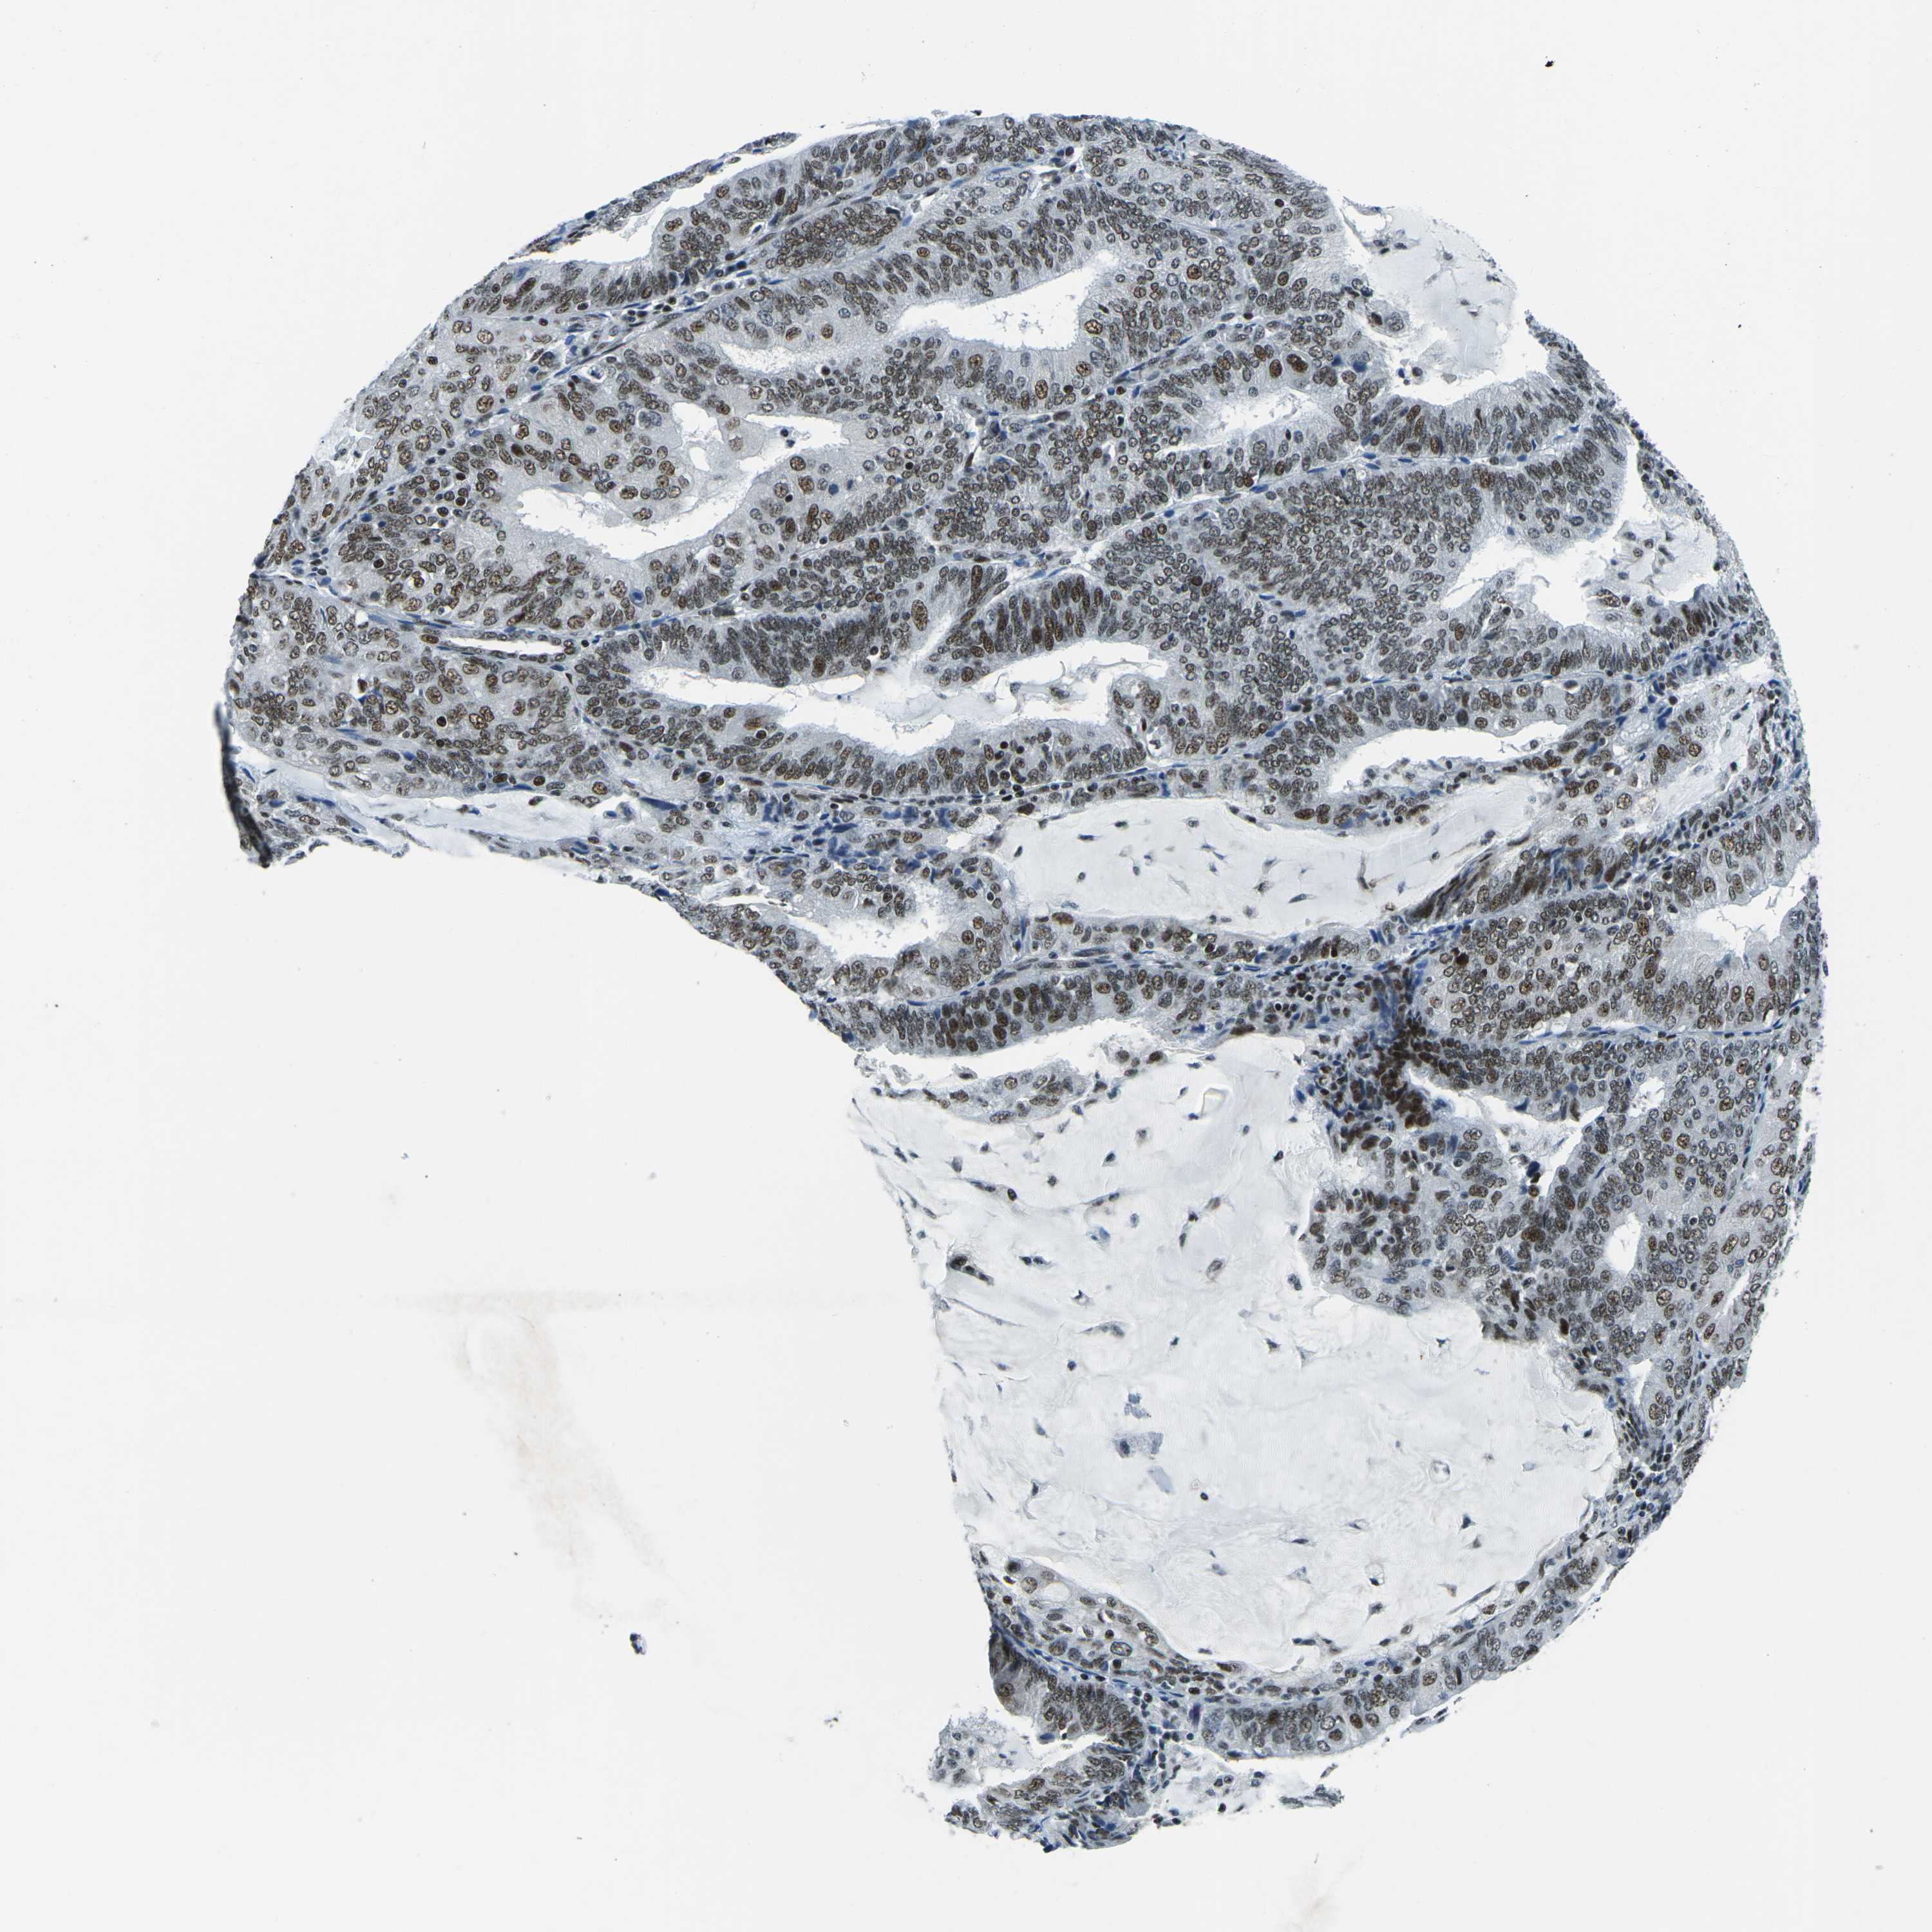

ENDOMETRIAL CANCER - Protein expressioni

A mouse-over function shows sample information and annotation data. Click on an image to view it in a full screen mode. Samples can be filtered based on level of antibody staining by selecting one or several of the following categories: high, medium, low and not detected. The assay and annotation is described here.

Note that samples used for immunohistochemistry by the Human Protein Atlas do not correspond to samples in the TCGA dataset.

Antibody stainingi

Antibody staining in the annotated cell types in the current human tissue is reported as not detected, low, medium, or high, based on conventional immunohistochemistry profiling in selected tissues. This score is based on the combination of the staining intensity and fraction of stained cells.

Each image is clickable and will lead to virtual microscopy that enables deeper exploration of all samples and also displays staining intensity scores, fraction scores and subcellular localization as well as patient and tissue information for each sample.

Antibody HPA019703

Antibody CAB016547

Staining

High

Medium

Low

Not detected

Intensity

Strong

Moderate

Weak

Negative

Quantity

>75%

75%-25%

<25%

None

Location

Nuclear

Cytoplasmic/membranous

Cytoplasmic/membranous,nuclear

Adenocarcinoma, NOS

Adenoma, NOS